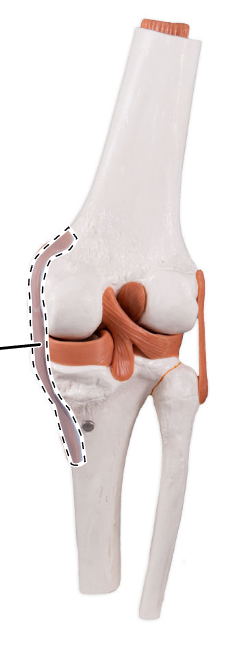

What is the joint shown here?

The tibiofemoral joint.

What is the joint shown here?

The tibiofemoral joint.

Lateral (fibular) collateral ligament.

What ligament is shown here?

Lateral (fibular) collateral ligament.